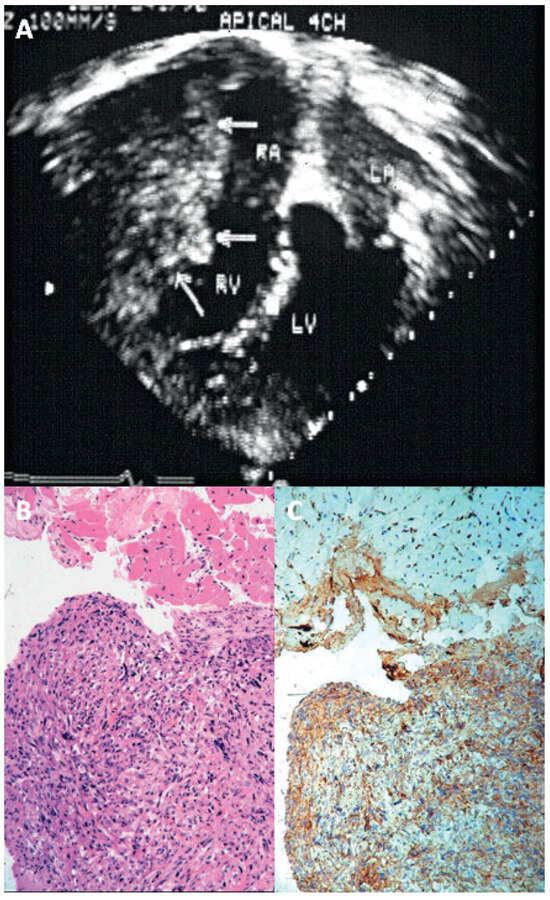

Prevalence and Pathology of Primary Cardiac Tumours

by Cristina Basso, Stefania Rizzo, Marialuisa Valente and Gaetano Thiene

Primary cardiac tumours are rare clinical observations, different from secondary neoplasms (ten times more frequent), and 90% of all primary cardiac tumours are benign. Myxoma is by far the most frequent benign tumour (75%), typically located in the left atrium, and manifests with [...] Read more.

Primary cardiac tumours are rare clinical observations, different from secondary neoplasms (ten times more frequent), and 90% of all primary cardiac tumours are benign. Myxoma is by far the most frequent benign tumour (75%), typically located in the left atrium, and manifests with intra-cavitary obstruction, embolism and constitutional symptoms, but it may also be silent and discovered incidentally by echo. Papillary fibroelastoma is a tumour usually arising on the valvular or mural endocardium, which, although quite small, may become symptomatic through embolic e vents. Typical tumours of the paediatric age group are fibroma, rhabdomyoma and teratoma. Primary malignant neoplasms account for 10% of all primary cardiac tumours and are represented by sarcomas (angiosarcoma, leiomyosarcoma, fibrosarcoma, liposarcoma, rhabdomyosarcoma undifferentiated pleomorphic sarcomas) and primary lymphomas. They usually infiltrate the cardiac walls, but may be also solely intra-cavitary, mimicking myxoma. Non neoplastic masses may consist of thrombi and infections, which again can be identified by a thorough surgical pathology examination. Cardiac non invasive imaging through transthoracic and transesophageal echocardiography easily detects heart masses. Cardiac magnetic resonance imaging a nd computed tomography are helpful complementary investigations, for refining diagnosis and in the post-surgery follow-up. Histology with immuno-histochemistry of any cardiac mass is mandatory for diagnosis, therapy and prognosis. Endomyocardial biopsy m ay be of help for histological investigation without thoracotomy particularly in right sided masses. Full article